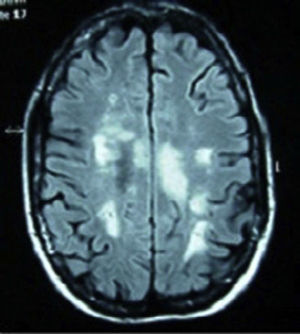

Clinical casesCase 1: 34-year-old Caucasian female, with a history of optic neuritis of the right eye 8 years ago. After admission due to abdominal discomfort, vomiting and fever, she presented 48h of ascending numbness and weakness of the lower limbs, urine and stool retention and decreased visual acuity of the left eye. During the interrogation in search of connective tissue diseases she referred xerostomia, xerophthalmia, vaginal and skin dryness. Neurological examination showed paraparesis with muscle balance of 1/5 in the left lower limb, 0/5 in the right lower limb and 2/5 in the right upper limb, diffuse hyperreflexia, extensor cutaneoplantar reflex, hypoesthesia for thermal sensitivity and in the painful D4-D5 dermatome, predominantly right deep sensitivity deficit in the left leg. Bilateral lower Schirmer test 5mm. Blood tests showed ESR 48mm/h, C-reactive protein 2.74mg/dl, antinuclear antibodies (ANA) speckled pattern +1/320, positive anti-Ro/SSA and aquaporin 4 antibodies and negative antiphospholipid antibodies. Vitamin B 12, folic acid, serology (syphilis, Brucella, Borrelia, HIV, HCV, HBV), Bence Jones protein, cryoglobulin, copper, serum levels of angiotensin converting enzyme, homocysteine and coagulation were normal. Magnetic resonance imaging (MRI) of cervical and thoracic spine: intramedullar lesion from C5 to D2. Cranial MRI (Fig. 1): presence of multiple lesions in the white matter on T2 and FLAIR. Evoked potentials: P100 response bilaterally elongated, being higher on the right side. Diagnosed with SS, treatment with boluses of methylprednisolone was initiated intravenously followed by oral prednisone at 50mg/day and azathioprine, achieving a progressive increase in visual acuity, although still with a temporal peripheral superior scotoma in the right eye. There was recovery of muscle balance and control of sphincters, walking without support at 15 months and without a new episode in the past 2 years.

Cranial MRI in T2 and FLAIR sequences, with presence of multiple lesions in the white matter at the subcortical, periventricular, periauricular and right corona radiata levels. The largest lesion extends from the posterior limb of the right internal capsule to the right mesencephalic peduncle.

Regarding diagnosis, MRI is the determining test. Studies show abnormality of signal with hyperintensity on T2, gadolinium enhancement and edema of the spinal cord. No specific images exist by etiology, although multiple small lesions seem indicative of SLE, while very extensive lesions and abnormalities at various levels are more indicative of vasculitis.12 On brain MRI in T2/FLAIR demyelinating lesions, with marked involvement can be found, as in our case 1. The study of cerebrospinal fluid may show inflammation of the spinal cord, with pleocytosis or elevated IgG values. In the basic immunological study we find antimyelin antibodies (which can predict the evolution of a clinically isolated syndrome to multiple sclerosis) and antiaquaporin 4 antibodies. Recurrence of TM has been associated with the presence of anti-Ro/SSA antibodies.13 However, it is precisely our case of SS with repeat episodes (case 2) which does not have anti-Ro/SSA or anti-La/SSB antibodies, basing the diagnosis on clinical and histological criteria.